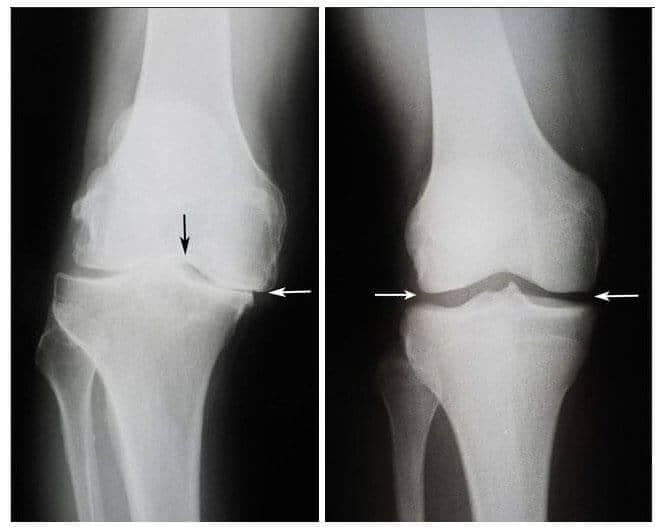

Potom sa stal skutočný zázrak. Tento lekár chodil každý deň k Pauline Bogzovej a rozmazaval nohy týmto terapeutickým gélom. Po šiestich týždňoch sa stáv kĺbov Pauliny Bogzovej zlepšil. Čo bolo tiež potvrdené rentgenovým žiarením.

Vľavo: Rentgen pravého kolena Pauliny Bogzovej - 75 rokov. Tkanivo chrupavky je takmer úplne zničené. Odporúčania lekára - nahradenie kĺbu protézou.

Vpravo: Rentgen pravého kolenného kĺbu Pauliny Bogzovej po použití Steplex.